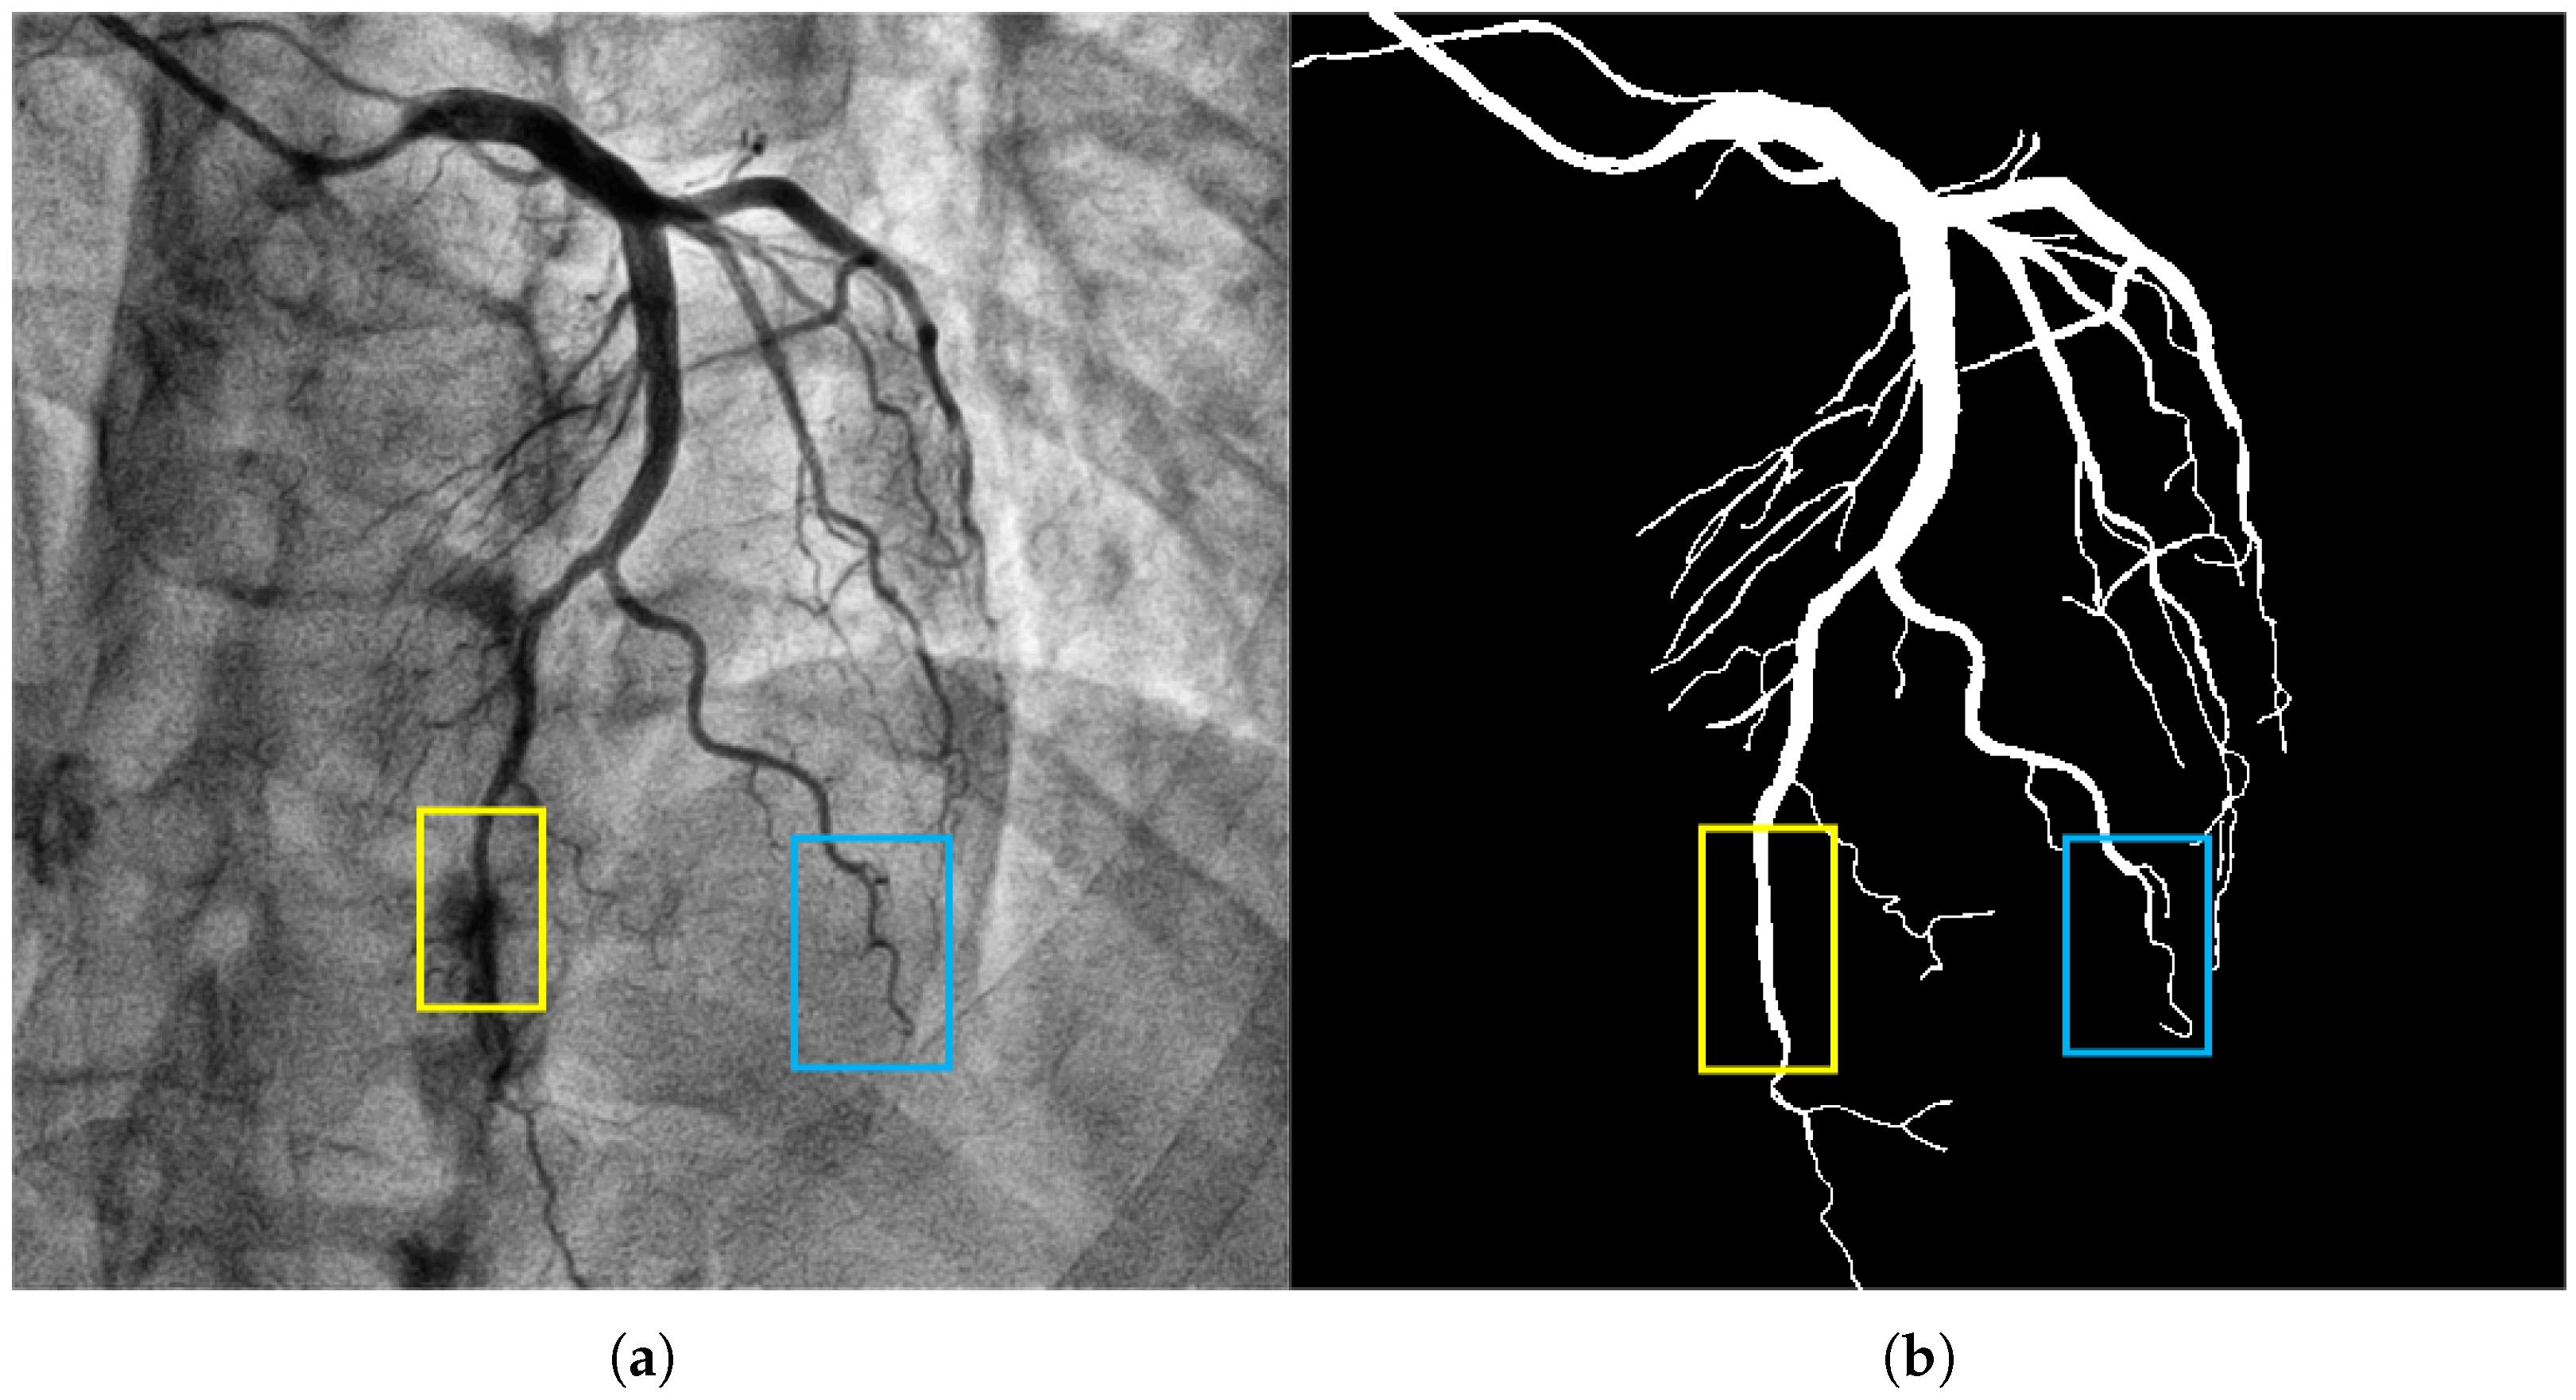

2.1. Analysis of Morphological Characteristics of Coronary Vessels

Cylindrical Feature

2.2. Key Issues in Coronary Vessel Segmentation

2.2.2. Connectivity Issues